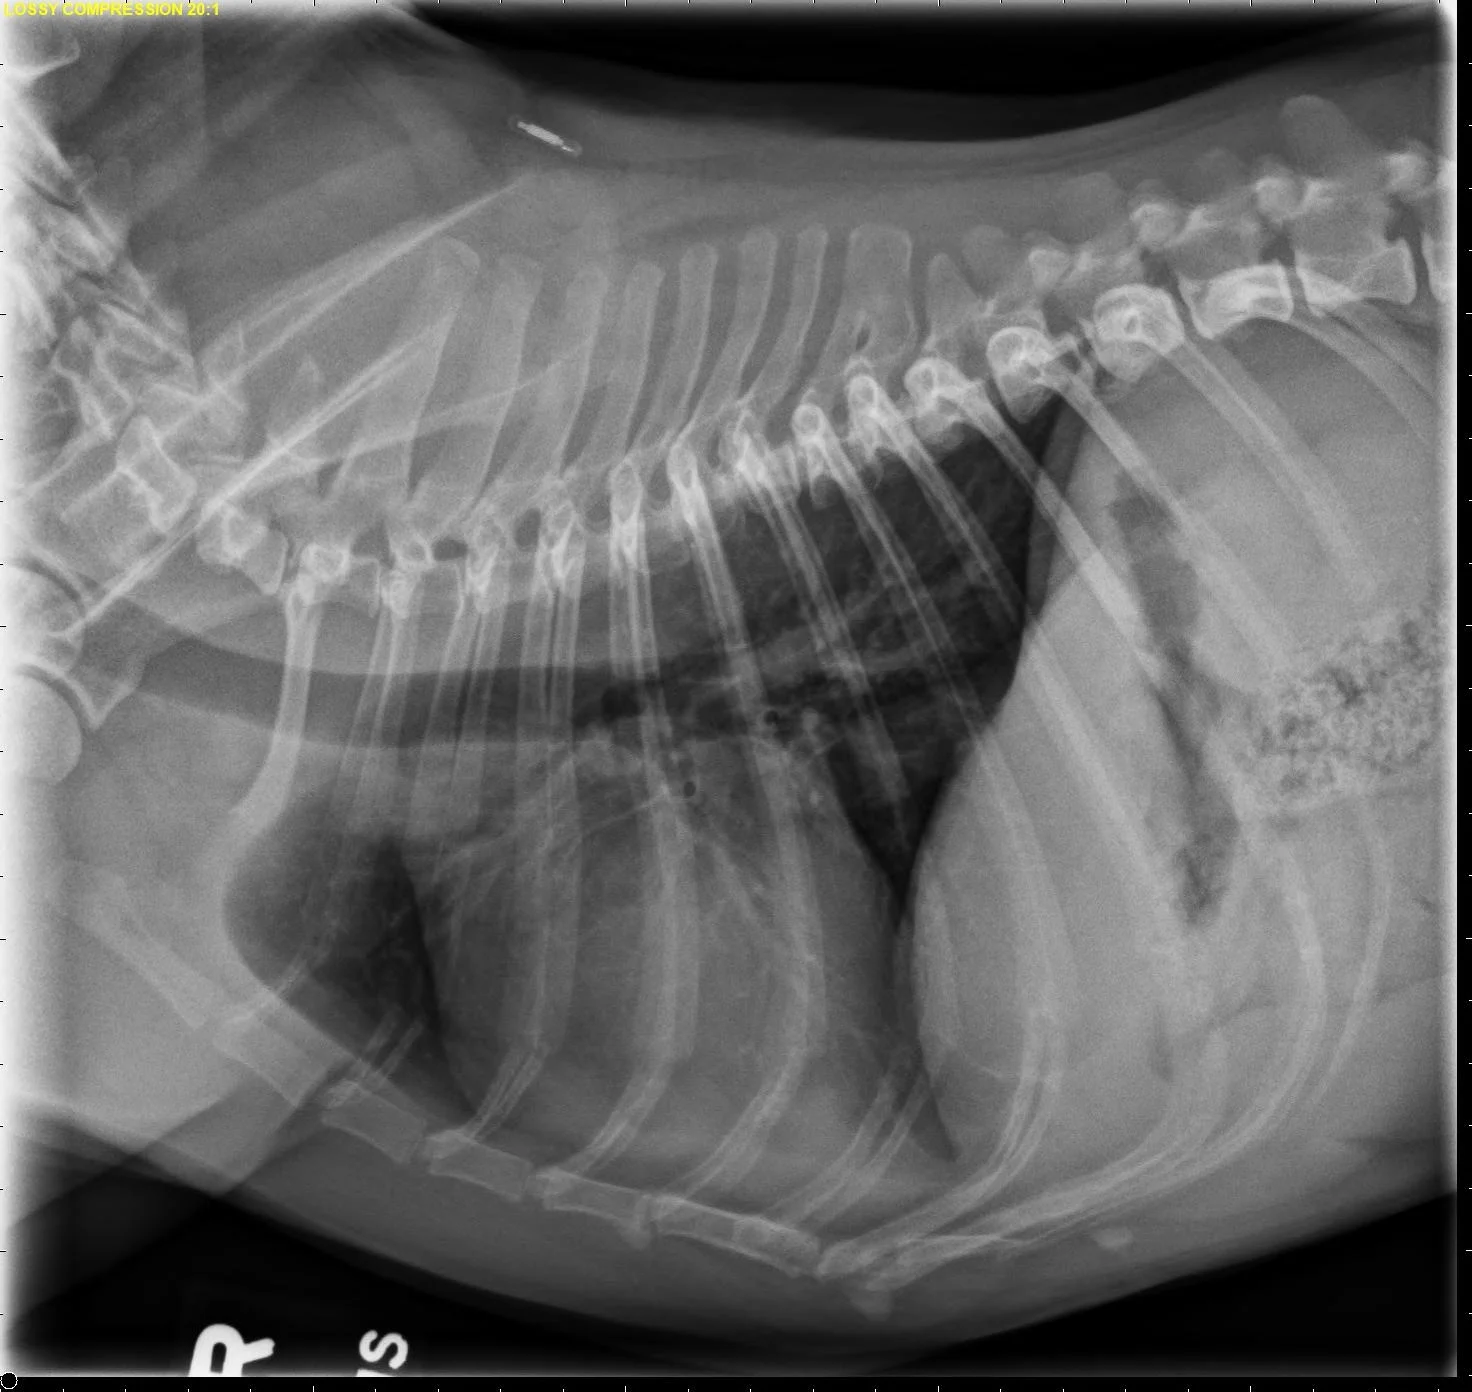

FIGURE 11 Right lateral (left) and VD (right) projections of a crossbreed dog with tricuspid valve dysplasia. The cardiac silhouette has increased width, and the regions of the right atrium and ventricle show roundness. The cardiac apex is displaced to the left secondary to right-sided enlargement (right). The caudal vena cava (arrowheads) is dilated, and there is loss of abdominal serosal detail secondary to increased systemic venous pressures and right-sided CHF, respectively. The pulmonary vasculature is small secondary to pulmonary hypoperfusion (given significant regurgitation across the tricuspid valve and decreased forward blood flow). VHS, VLAS, M-VLAS, and VRHi collected from the right lateral view are 12.3, 2.3, 2.7, and 3.8, respectively. Images courtesy of Bruna Del Nero, DACVIM (Cardiology)